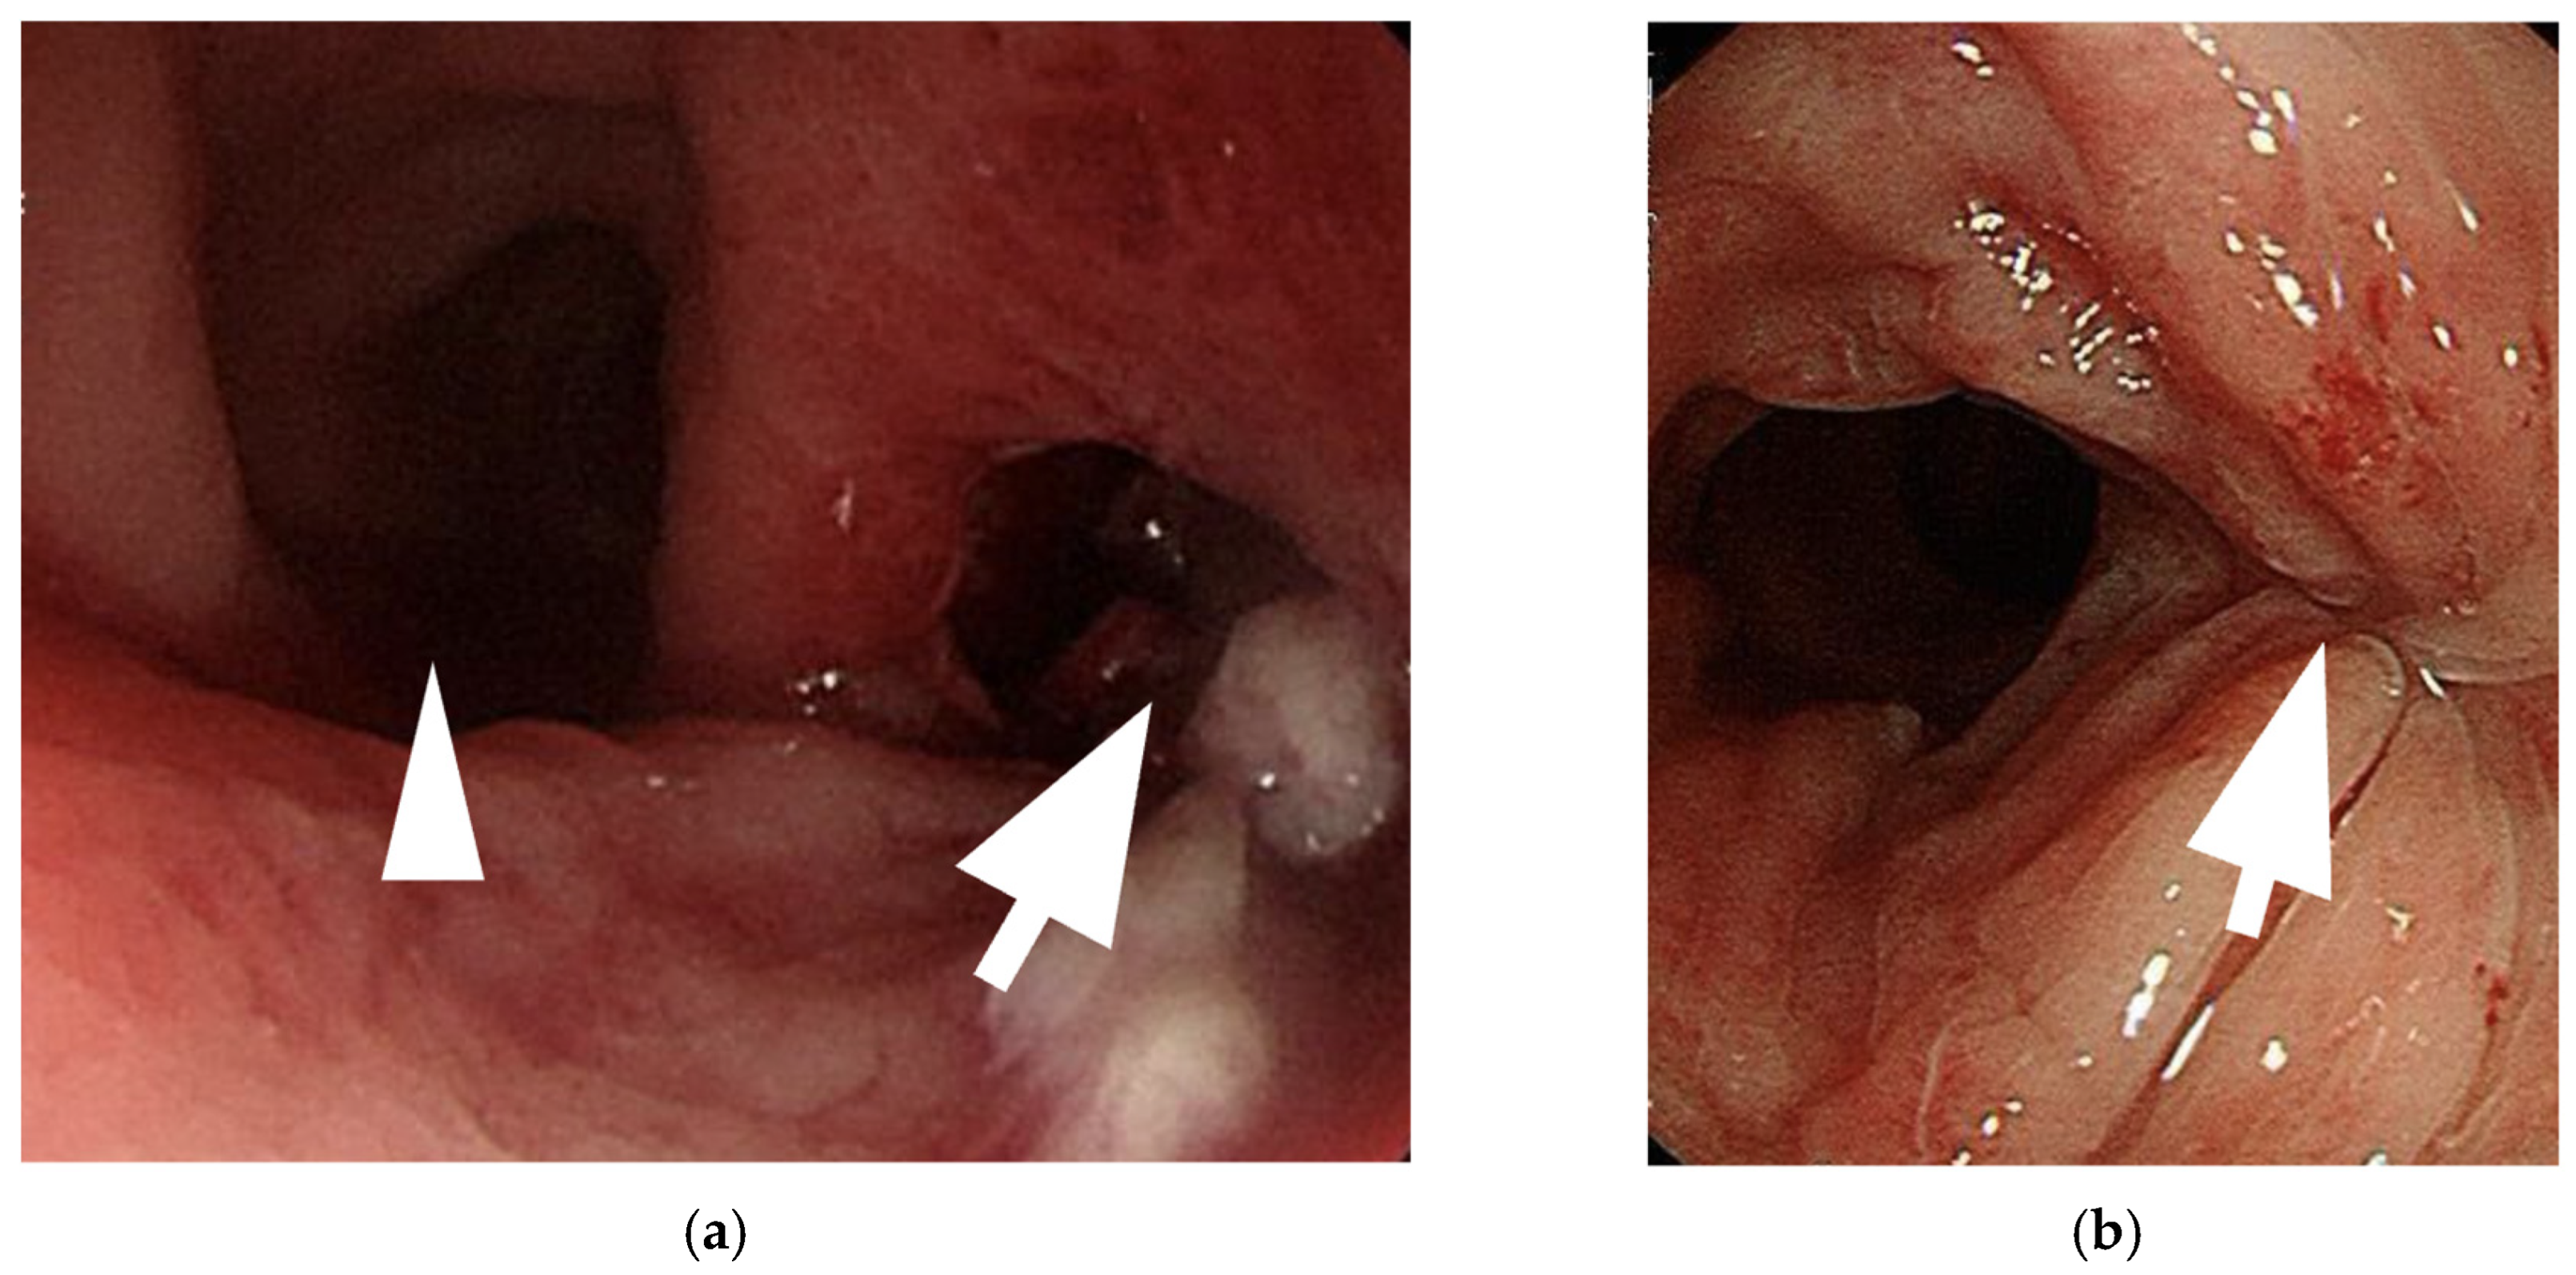

- Shimamura et al. (2015) described a case of neovaginal perforation complicated by an intra-abdominal abscess, where the clinical symptoms and radiologic findings were incongruent [18]. Surgical intraperitoneal drainage was performed due to concerns that the abscess might not resolve with antibiotics alone.

| Image findings | A large amount of fetid mucus in the abdominal cavity via laparoscopy |

| CT: a massive abscess occupying a significant portion of the intra-abdominal cavity |